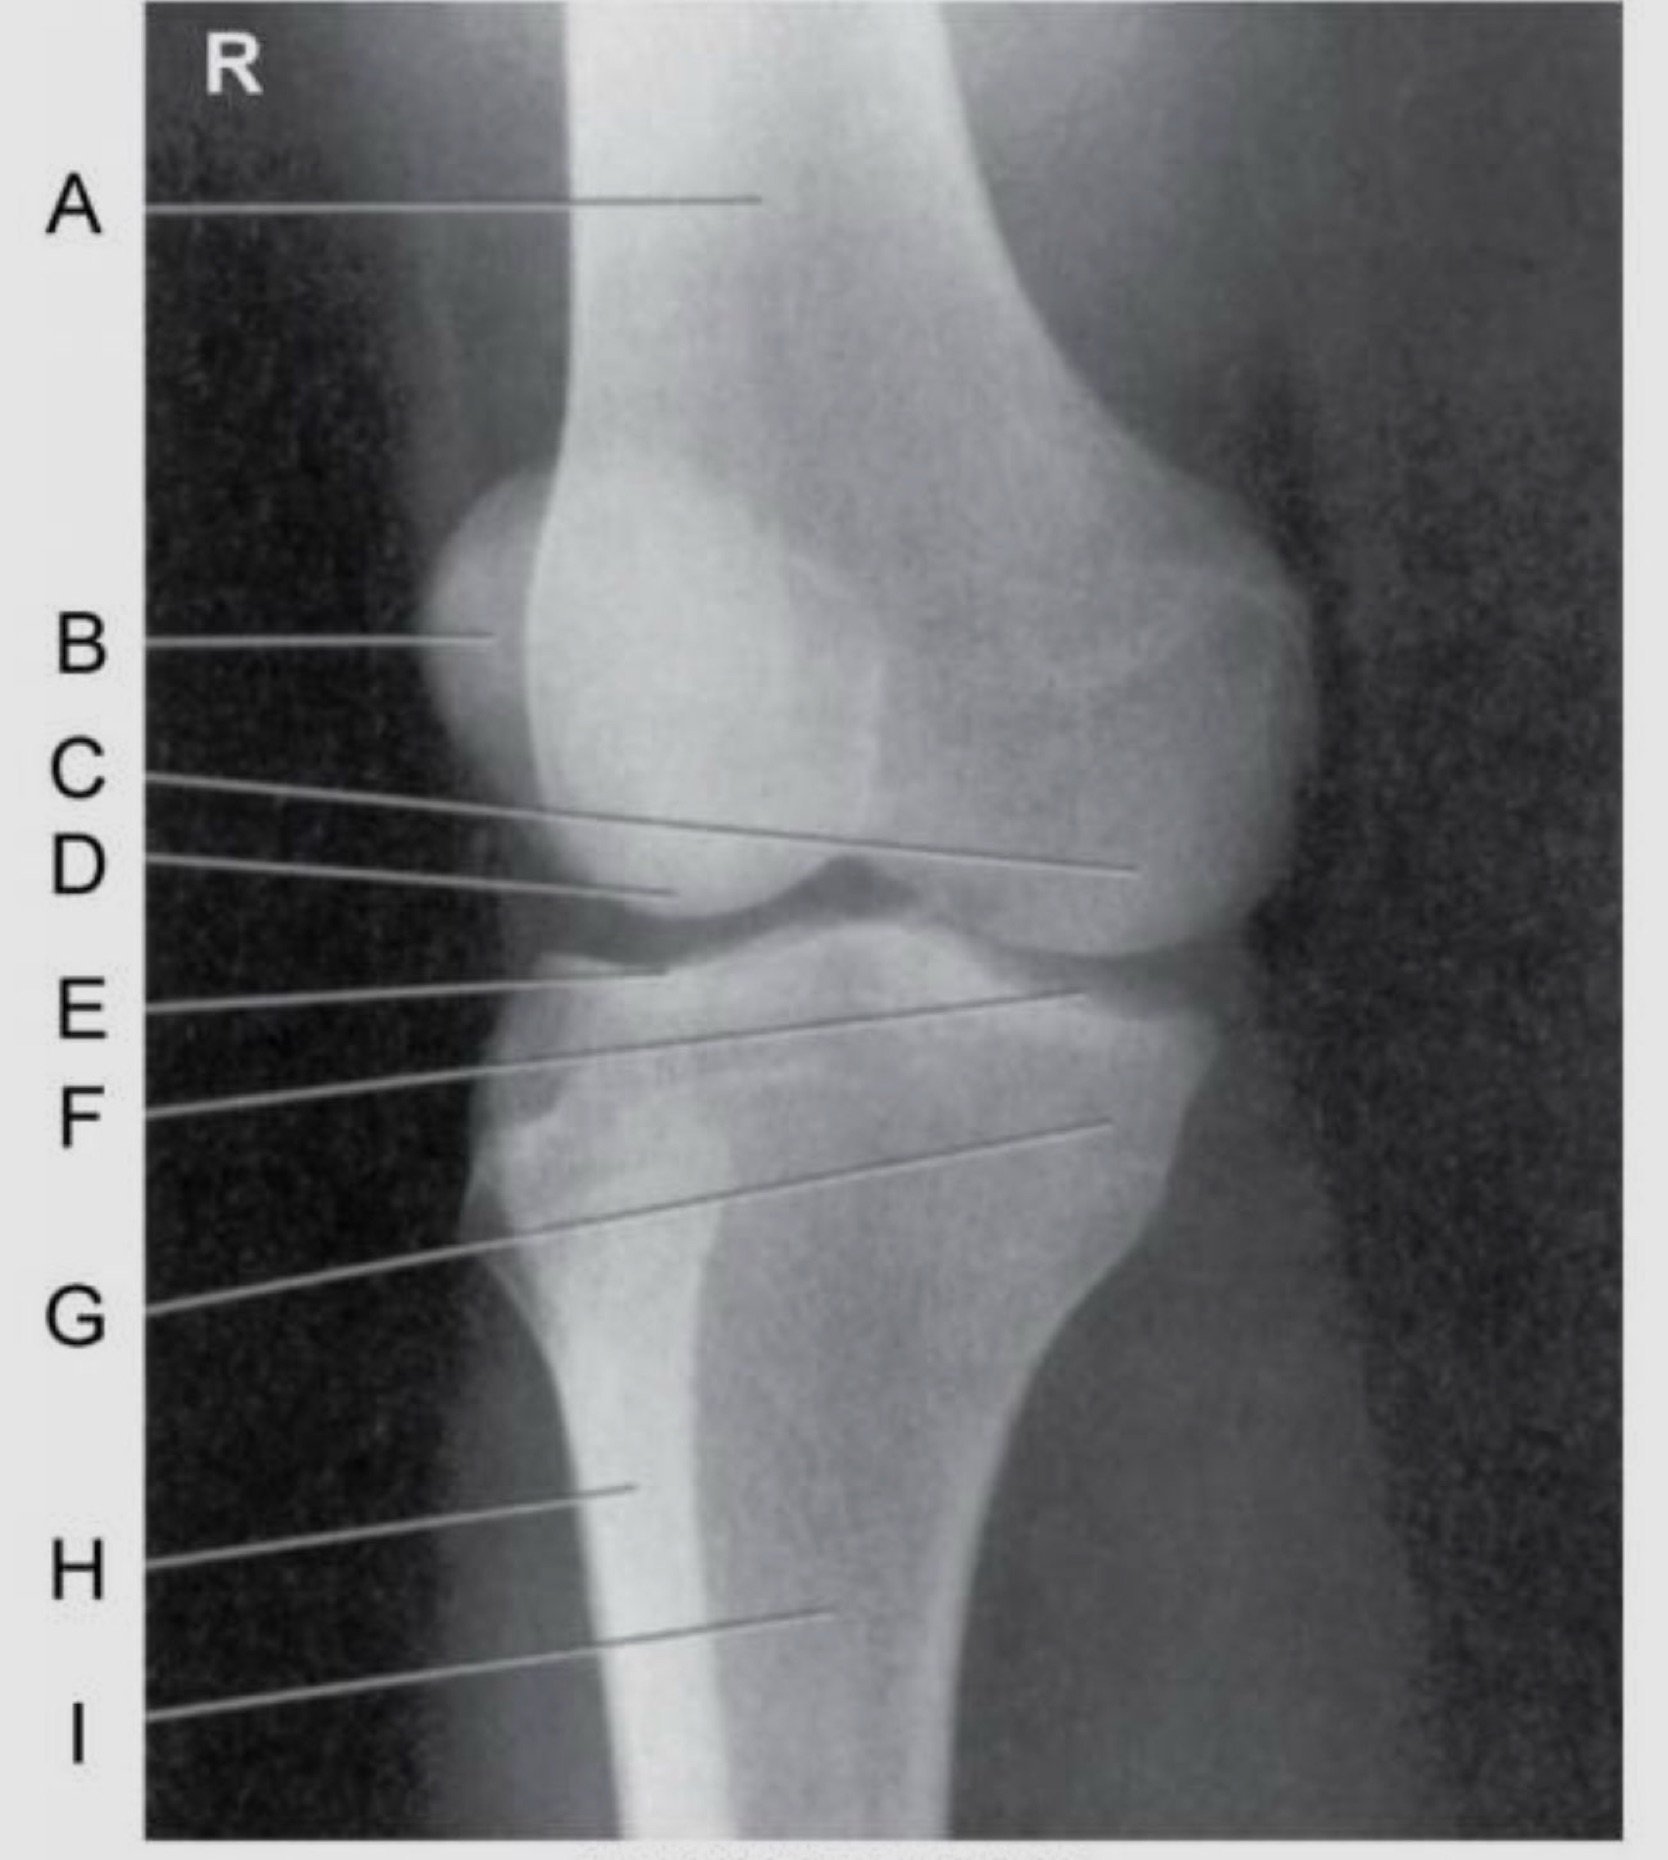

Name the projection.

Should it be repeated, if so why?

AP Internal (Medial) Oblique

No.

Label the image.

A) Femur

B) Patella

C) Medial femoral condyle

D) Medial tibial condyle

E) Tibia

F) Fibula

G) Lateral tibial condyle

H) Intercondylar eminence(s)

I) Lateral femoral condyle